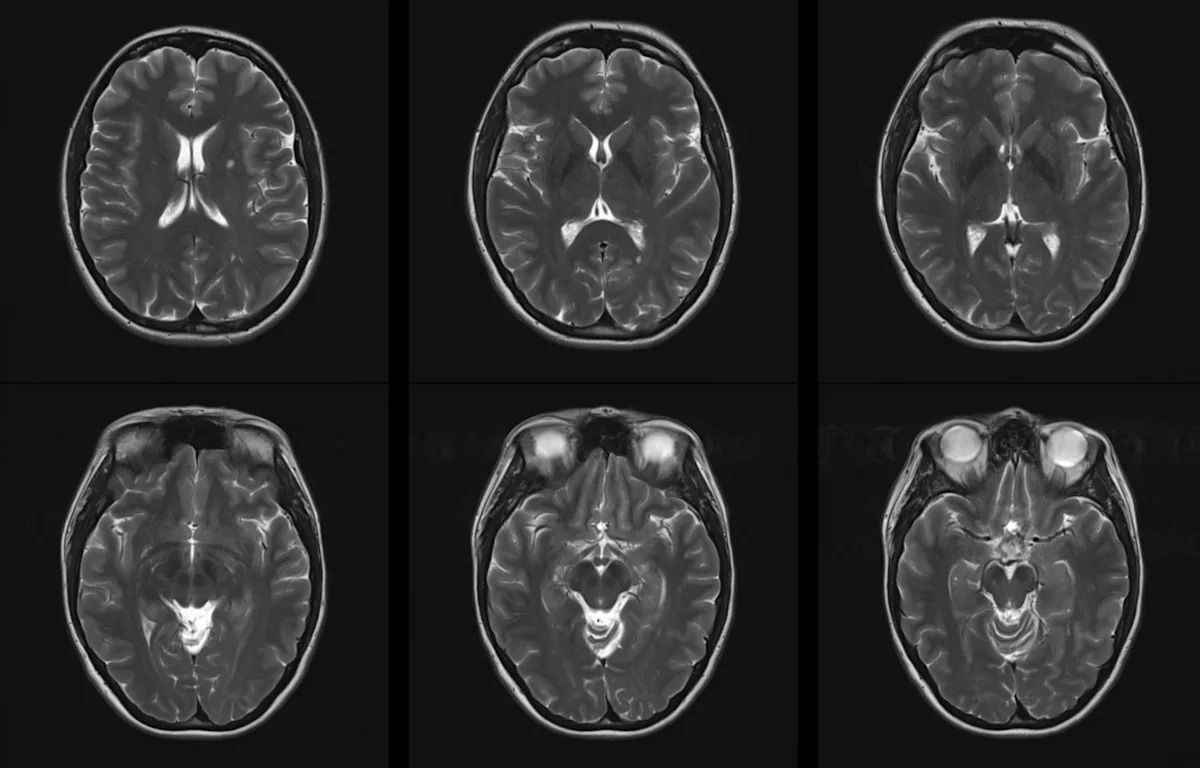

Air pollution's reputation as a "silent killer" is well-earned. New research indicates that dirty air is also linked to raising the risk of developing multiple sclerosis and worsening the disease for those already suffering from it. Multiple Sclerosis News Today wrote about a new study published in the Annals of Clinical and Translational Neurology that explored the relationship between air pollution and MS. The review analyzed 22 studies involving over 16 million people and looked at pollutants such as particulate matter as well as airborne chemicals such as carbon monoxide and sulfur dioxide. Researchers found a 21% increased risk of MS with long-term exposure to fine particulate matter with diameters under 2.5 micrometers (aka PM2.5) and a 20% increase for slightly larger particles of under 10 micrometers. No significant association for developing MS was found for other pollutants, such as carbon monoxide and sulfur dioxide. People already contending with MS weren't so lucky. Short-term exposure to particulate matter and all of the other pollutants was linked to at least one, if not all, of the negative impacts like lesions, worsening disease, or heightened relapse risk. Public health experts stress the importance of cleaner air, and this study provides even more backing for that mission by illuminating a worrisome relationship between air pollution and MS. "Our study provides strong evidence of the association between air pollution and risk of developing MS and severity of MS including relapses, developing CELs [contrast-enhancing lesions], and disability progression," the scientists wrote. MS is a devastating disease impacting 2.8 million people worldwide, including many young adults. The disease creates an economic burden of over $85 billion in the U.S., per the study. Air pollution is a worldwide problem affecting 99% of the global population, according to the World Health Organization. It says that is responsible for nearly 7 million premature deaths annually. Which of these savings plans for rooftop solar panels would be most appealing for you? Save $1,000 this year Save less this year but $20k in 10 years Save less in 10 years but $80k in 20 years Couldn't pay me to go solar Click your choice to see results and earn rewards to spend on home upgrades. Events like wildfires and persistent smog can lead to dangerous conditions for residents to breathe in. These conditions' links to MS add even more reason to be wary of polluted air. Efforts to improve air quality, such as increasing the use of electric vehicles, are ongoing. Studies in California show a major reduction in pollutants through EV adoption. Other measures, such as the Clean Air Act in the U.S., are in place to protect citizens from polluted air from industrial sources. Getting away from energy sources that add more pollution to the air, like oil and gas, is another important move. The movement toward wind and solar power can help clean the air over time. Get TCD's free newsletters for easy tips to save more, waste less, and make smarter choices — and earn up to $5,000 toward clean upgrades in TCD's exclusive Rewards Club.